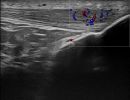

Αγγεία και Νεύρα Γόνατος

- Θρόμβωση στην Ιγνυακή Φλέβα

- Ανεύρυσμα στην Ιγνυακή Αρτηρία